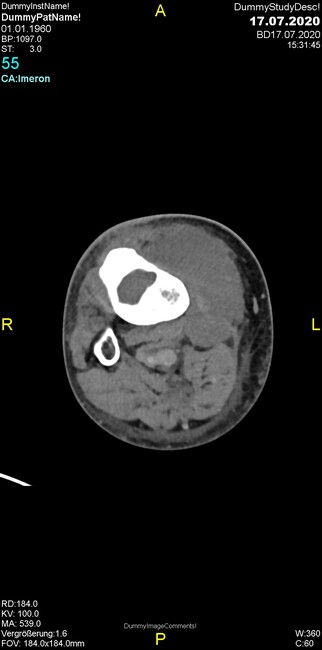

Um welche Modalitäten handelt es sich?

- Röntgen p.a. und lateral, CT coronar Knochenfenster, CT axial Weichgewebsfenster

Was fällt in der Projektionsradiographie auf?

- Verdichtung im Recessus suprapatellaris

- Aufhellungslinie in Projektion auf die Femurkondylen

Was trifft auf den Befund zu?

Was fällt in der CT im Knochenfenster auf?

- Osteolyse der Tibiametaphyse unter Beteiligung der Kortikalis

Was kommt differentialdiagnostisch in Frage?

- Osteomyelitis mit Weichgewebsanteil

- Metastase mit pathologischer Fraktur